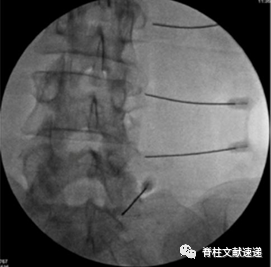

关节突关节封闭